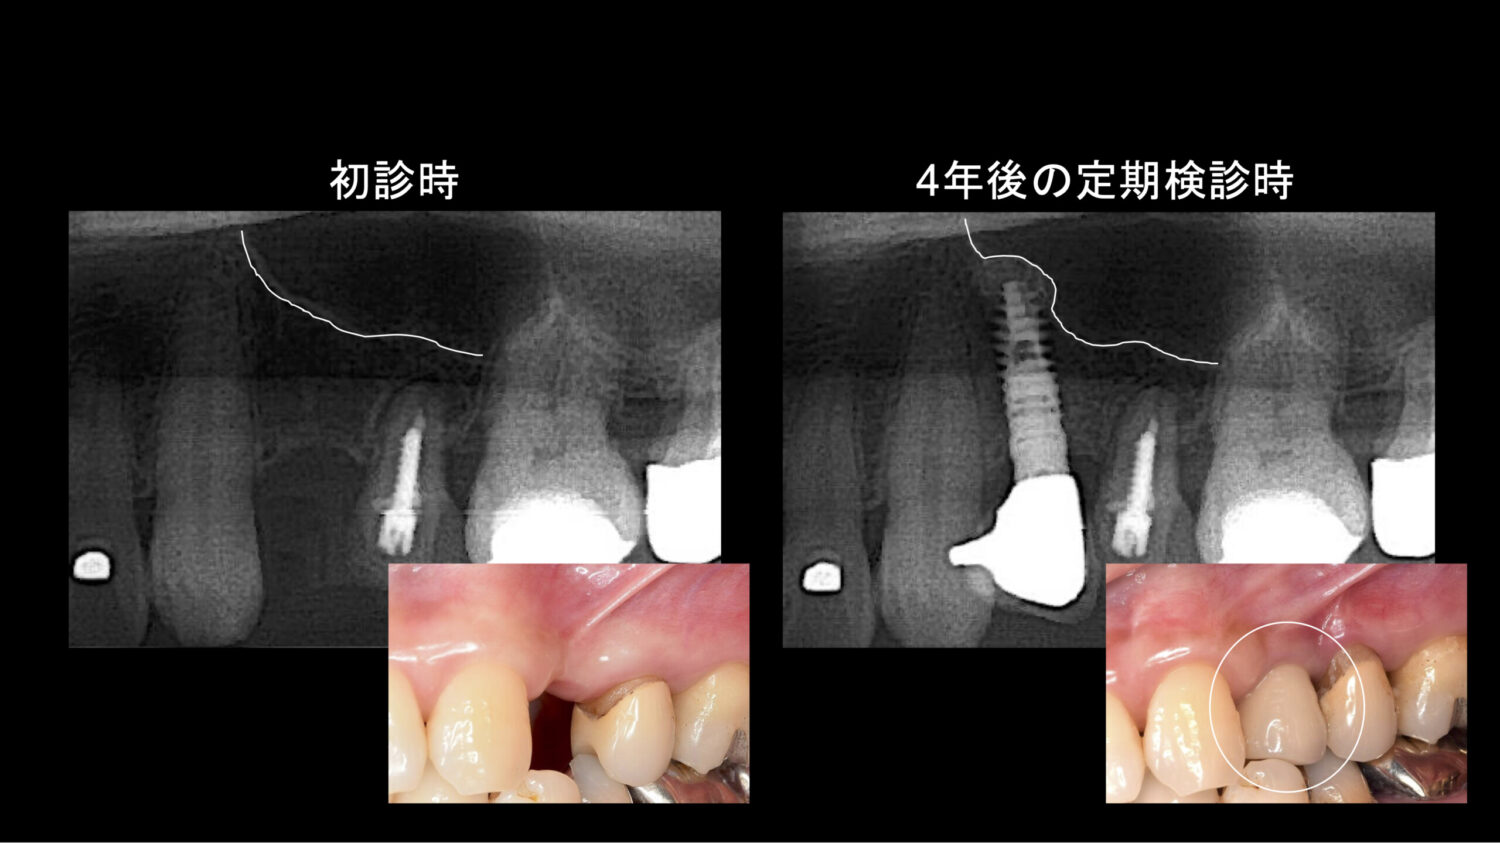

治療前・治療後の比較写真とレントゲン

入れたいインプラントの長さや幅が不足していた分の骨も形成され、歯のない部分にインプラントが入り、歯ぐきも形成することで、歯ぐきの凹みなどが改善しました。レントゲンでは明らかにインプラントを支える骨ができているのがわかります。患者様は、しっかりと噛める感覚が戻り、入れ歯のわずらわしさから解放されたことに満足されていました。